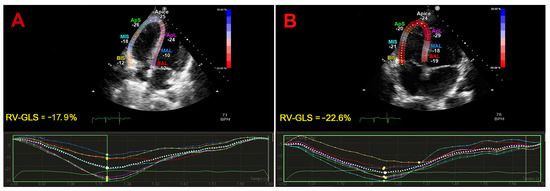

3.4. Effect of IPF on RV-GLS

| RV-GLS (%) | 18.6 (13.4–22.6) | 22 (18.4–24.2) | <0.05 | 6 (100) |